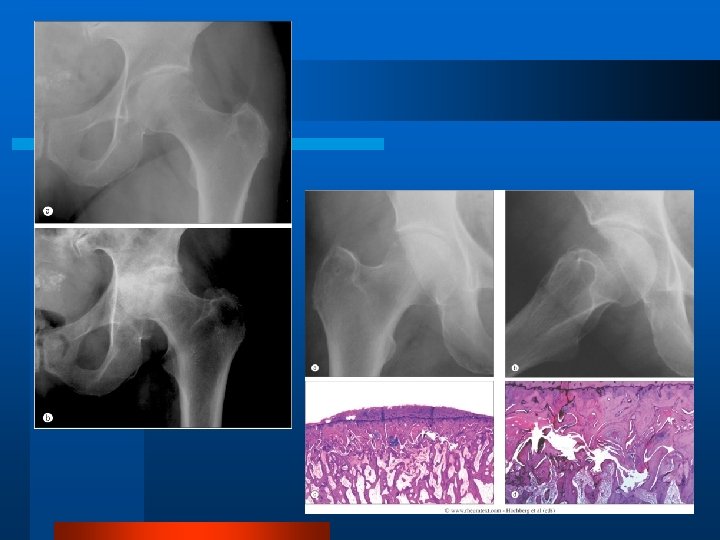

Examenul radiologic l Radiografia simplă este cel mai util mijloc imagistic în artroză, atât pentru diagnostic, cât şi pentru urmărirea evoluţiei. Aspectul l Îngustarea spaţiului articular l Scleroză subcondrală l Osteofitoză marginală l Pseudochisturi sau geode

Gradarea Kellgren-Lawrence 0: Normal I: Osteofite posibile şi posibil pensarea spaţiului articular II: Osteofite definite şi posibil pensarea spaţiului articular III: Osteofite moderate multiple, pensarea definită a spaţiului articular, scleroză şi posibil deformare a conturului osos IV: Osteofite mari, pensarea marcată a spaţiului articular, scleroză severă, şi deformare definită a conturului osos

Criterii de Diagnostic Coxartroza (artroza şoldului) Dureri în şold în majoritatea zilelor pe parcursul lunii precedente 2. Existenţa osteofitelor în şold şi/sau în acetabulus 3. VSH ≤ 20 mm/oră 4. Limitarea rotaţiei interne a şoldului 1. Diagnosticul OAD se stabileşte în baza existenţei punctelor 1 şi 2 sau punctelor 1, 3 şi 4. Sensibilitate 91 %, specificitate 89 %.